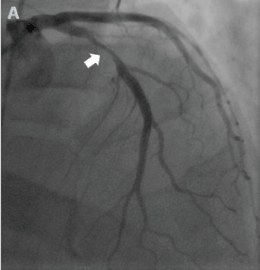

All baseline labs were normal except Troponin I which was found to be mildly elevated. Chest X ray and echocardiography was normal. Patient underwent Coronary angiography which showed severe proximal LAD stenosis (Figure 3) and that Brugada pattern came out to be Brugada phenocopy seen in V1 and V2 .

Figure 3. Coronary Angiogram showing severe disease in Proximal LAD